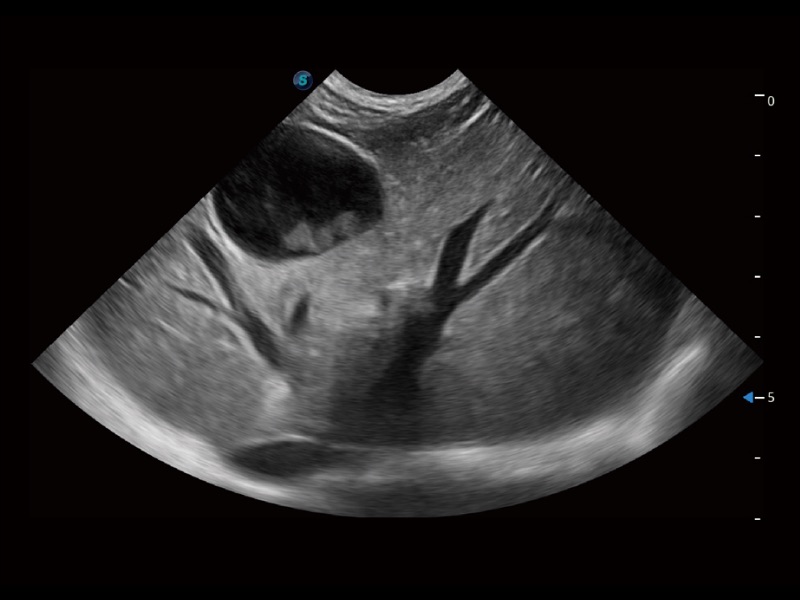

ProPet 70專為動物醫(yī)生設(shè)計(jì),對不同的動物體型和生理結(jié)構(gòu)作出了針對性的優(yōu)化。通過動物影像專用軟件,可滿足個性化的應(yīng)用需求,幫助動物醫(yī)生獲得更精確的診斷數(shù)據(jù)。

為精細(xì)結(jié)構(gòu)及組織邊緣提供高清晰度的圖像和更大的成像視野。幫助減輕醫(yī)生的用眼疲勞,快速精準(zhǔn)獲得測量的數(shù)據(jù)。